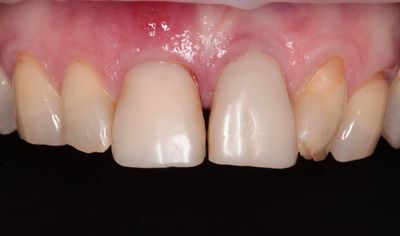

45-ročná pacientka sa obrátila na našu kliniku s bolesťou v oblasti horných stredných rezákov (obr. 1). Pri dôkladnom vyšetrení a CT diagnostike bola v oblasti zuba č. 11 zistená vertikálna fraktúra koreňa (obr. 2). V oblasti zuba č. 21 palatinálne bol prítomný hlboký kaz koreňa (obr. 3).